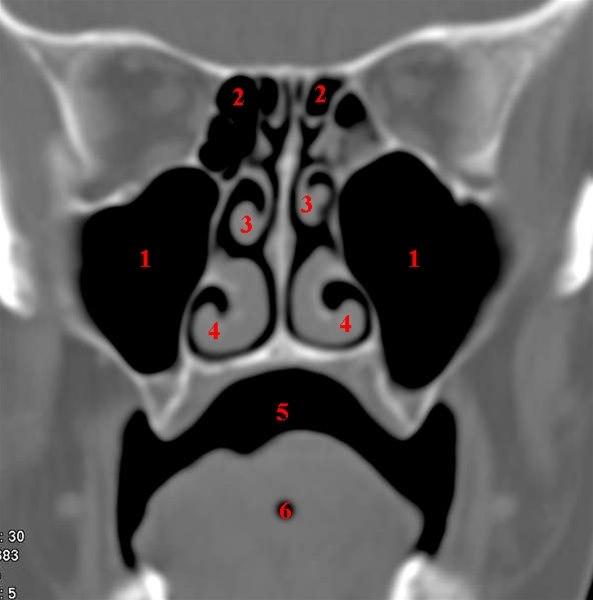

CT-snitt i coronalplan gjennom maxillarsinus

- Sinus maxillaris

- Sinus ethmoidales

- Concha nasalis media

- Concha nasalis inferior

- Cavum oris (munnhule)

- Lingula (tunge)